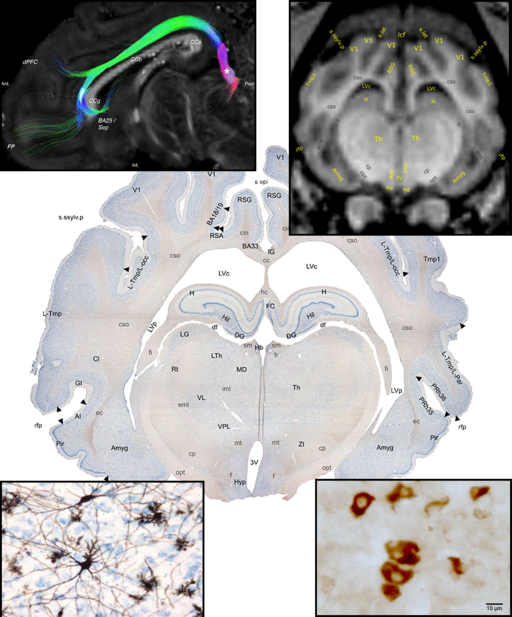

Preclinical studies and disease modelling are not possible without a thorough knowledge about brain anatomy and physiology. Therefore, an important part of CENSE group activity is studying the neuroanatomy and histology of the brain of our model animals, with a focus on Göttingen minipigs. Portfolio of the techniques used by us to describe the anatomy includes neuroimaging (MRI imaging, MRI-DWI tractography), reconstruction of the brain connectivity using stereotactically injected neuronal tracers (e.g. fluorogold or BDA) and various histochemical or immunohistochemical methods. Our experiments require good knowledge of the targeted structures, therefore we described in details various areas of the Göttingen minipig brain (like the subthalamic nucleus, substatia nigra, hypothalamus, septum, nucleus accumbens and so on), what, together with Nissl stained sections, allowed us to construct and publish first Gottingen minipig brain atlas, freely available online. The atlas includes also described MRI images and serve as a useful tool for researchers working with minipigs. The experiments performed by our group often require a post-mortem tissue analysis, therefore, we are constantly working on the development of the techniques for minipig brain removal and sectioning, histological staining and subsequent tissue analysis (using both quantitative (stereology and image analysis) and qualitative methods). Our group use those methods to describe nervous tissue response in various conditions, like diseases modelling, testing new devices (e.g. DBS electrodes), or new treatment paradigms (e.g. implanted stem cells).

Neurostereology and neurohistology

Our research activity often requires a post-mortem analysis of the nervous system tissue. This may be basic research concerning Göttingen minipig anatomy, translational studies and disease modelling or verification of the new surgical techniques (like testing new brain-machine interfaces, verification of the precision of the stereotactic surgery etc.). Handling of the relatively large (in comparison with rodents) minipig brain is not simple. Therefore, CENSE group developed several techniques for animal perfusion, brain extraction, tissue slicing, freezing and processing using various histological techniques. Our neuro-histo-lab has extensive experience with processing of the nervous tissue using a variety of techniques, for frozen and paraffin-embedded samples. In many cases, the qualitative description of the histological sections is not sufficient; therefore, we are using also quantitative methods. Image analysis allows us to estimate several parameters describing the histological images, like area covered by the staining, morphology of the cells (using various shape descriptors) or changes in the dendritic spine density. Our group have also experience with stereology, used for unbiased estimation of the number of cells or fibers as well as volumes of various brain parts.

Cense group have extensive experience with the use of various imaging techniques in neuroscience-related research using large animals (pigs and minipigs) under anesthesia. The size of the pig/minipig brain allows us to use standard clinical imaging modalities. Routinely, we are using anatomical and stereotactic MRI in the planning of the surgeries and evaluation of their outcome (verification of the electrode placement, effects of the electrocoagulation etc.) as well as in the long term studies (like the evaluation of the effect of radiation on the nervous tissue). Designed by our group MRI compatible localizer box and stereotactic frame allows us to precise targeting of various minipig brain structure. We have also experience with ex-vivo, post mortem MRI and fiber reconstruction. Other imaging techniques used by us include computed tomography (CT), positron emission tomography (PET - used in the analysis of the brain activity or dopaminergic neurotransmission studies) or X-ray imaging (fluoroscopy). Our group have established close collaboration with the PET Centre and Center of Functionally Integrative Neuroscience (CFIN) MRI group, localized in the Aarhus University Hospital, allowing us to test various imaging paradigms.